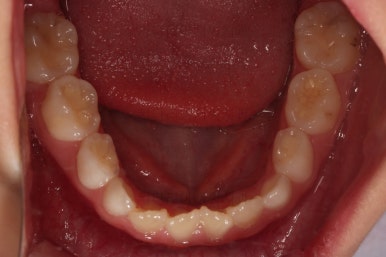

위턱뼈가 가로로 넓어지니 앞니 사이에도 공간이 많이 생겼네요.

부분적으로 교정장치를 부착해서 당사자가 제일 고치고 싶어햇던 앞니 부분을 가지런하게 하기 시작했어요.

위턱뼈가 앞으로도 점점 나와서 처음 보다는 반대교합 경향이 개선되고 있는게 보이네요.

앞니도 굉장히 가지런해졌고요.

반대교합 경항도 거의 없어졌어요.